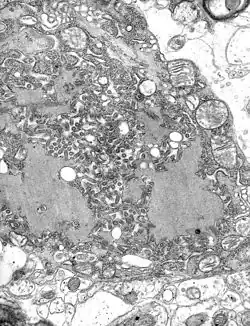

Colorized transmission electron micrograph showing the rabies virus (in red) infecting cultured cells

TEM micrograph with numerous rabies virions (small dark-grey rod-like particles) and Negri bodies (the larger pathognomonic cellular inclusions of rabies infection)